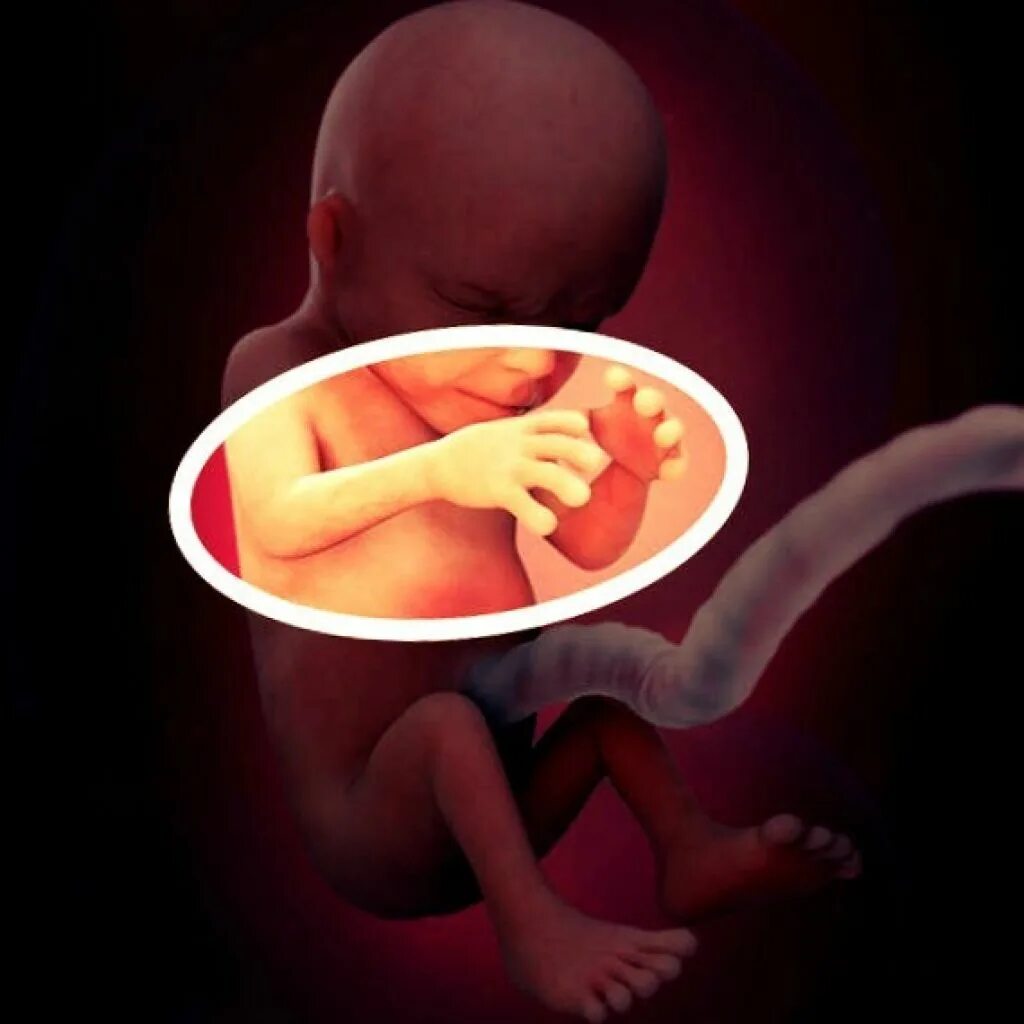

18 недель как выглядит малыш